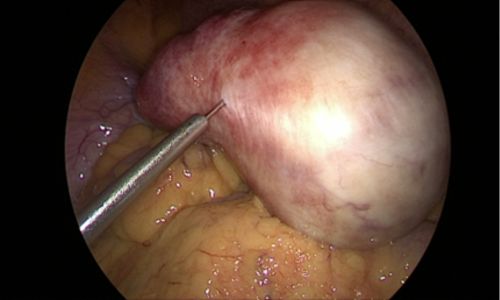

During surgery, no incisions were made on the abdominal wall. The procedure was performed through the natural birth passage using a hysteroscope, which allowed direct visualisation of the uterine cavity. The fibroid was identified & removed using an energy source.

Unlike traditional surgery, no abdominal cuts or stitches are required. A hysteroscope, a thin telescope-like instrument, is inserted through the vagina & cervix into the uterus. The fibroid is directly visualised & removed using an energy source or resectoscope.